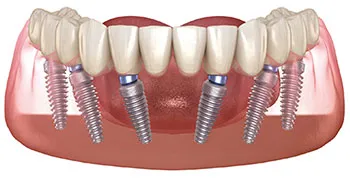

Full Mouth Dental Implants

Sometimes due to extensive cavities or advanced periodontal disease, all of the teeth need to be removed. In these cases, a full arch fixed (non-removable) restoration will be fabricated. This will both restore your smile and ability to chew normally.

Sometimes due to extensive cavities or advanced periodontal disease, all of the teeth need to be removed. In these cases, a full arch fixed (non-removable) restoration will be fabricated. This will both restore your smile and ability to chew normally.

The teeth are extracted and at least 6 implants are placed per arch. After the implants heal for approximately three months, the final set of teeth are fabricated, customized to the patient’s implants and facial features.